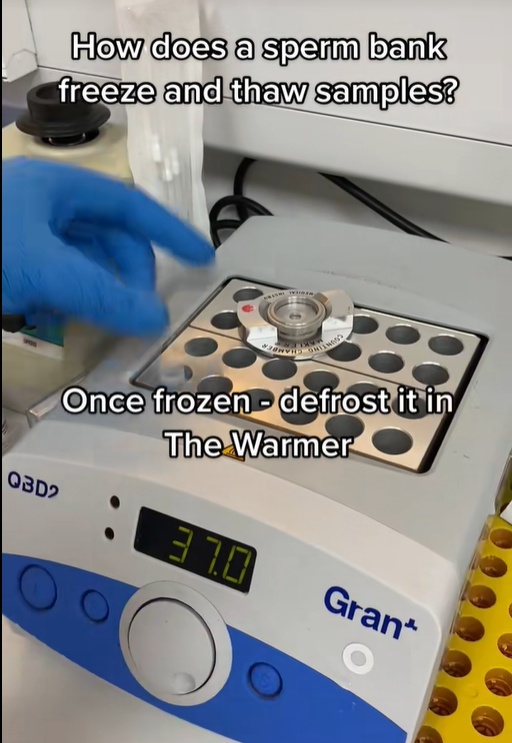

Το σπέρμα ελέγχεται επίσης για να διασφαλιστεί ότι μπορεί να επιβιώσει από την κατάψυξη και την αποθήκευση σε τράπεζα σπέρματος.

Διαδικασία απόψυξης δείγματος σε εργαστήριο τράπεζας σπέρματος, όπου το γενετικό υλικό διατηρείται σε ελεγχόμενες συνθήκες πριν από τη χρήση του